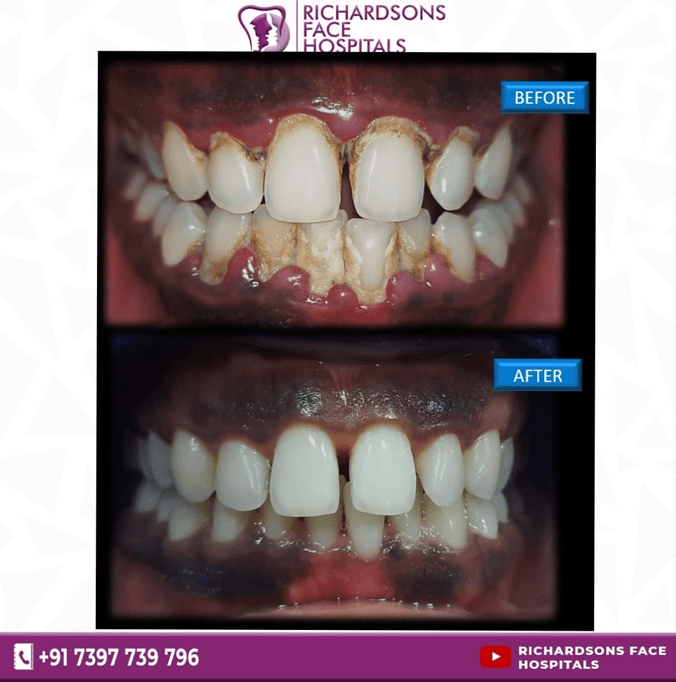

ADVANTAGES OF TEETH CLEANING:

- Regular cleaning can remove all the food debris, calculus, and plaque

- Prevents gingivitis and periodontitis

- Polishing can prevent further deposition

- Dental scaling is a professional cleaning of your teeth in which the plaque, calculus and the extrinsic stains can be removed from the surface of the teeth and also below the gumline

- Polishing will be done after scaling so that it prevents further deposition of the plaque and the calculus.